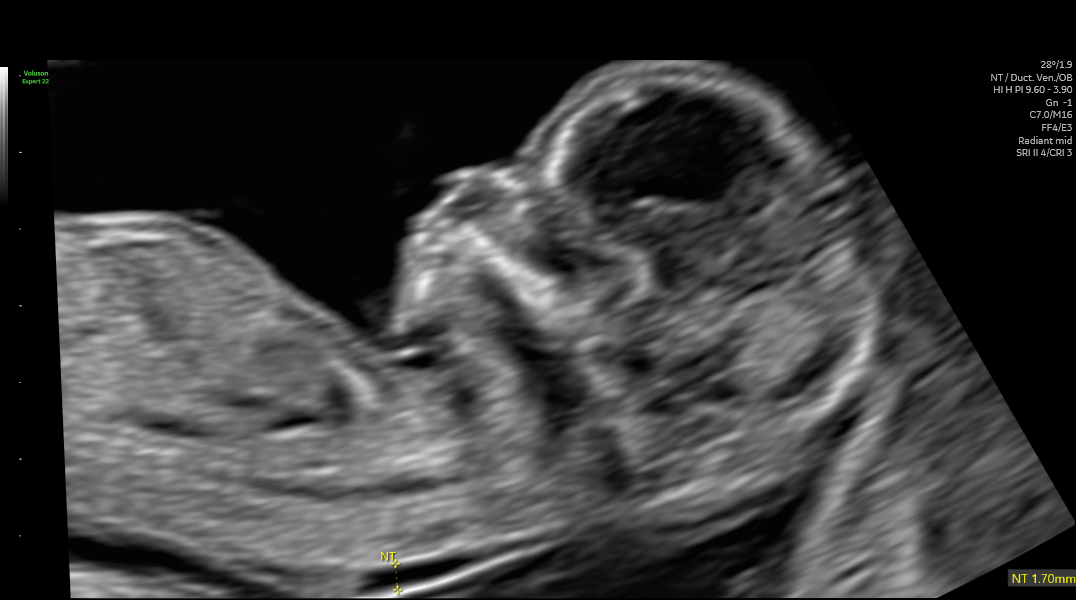

At the time of writing my wife is 18 weeks pregnant with a baby boy, and the scans and testing indicate that he is healthy and getting ready to take on the real world.

Sonar of our baby boy at 13 weeks